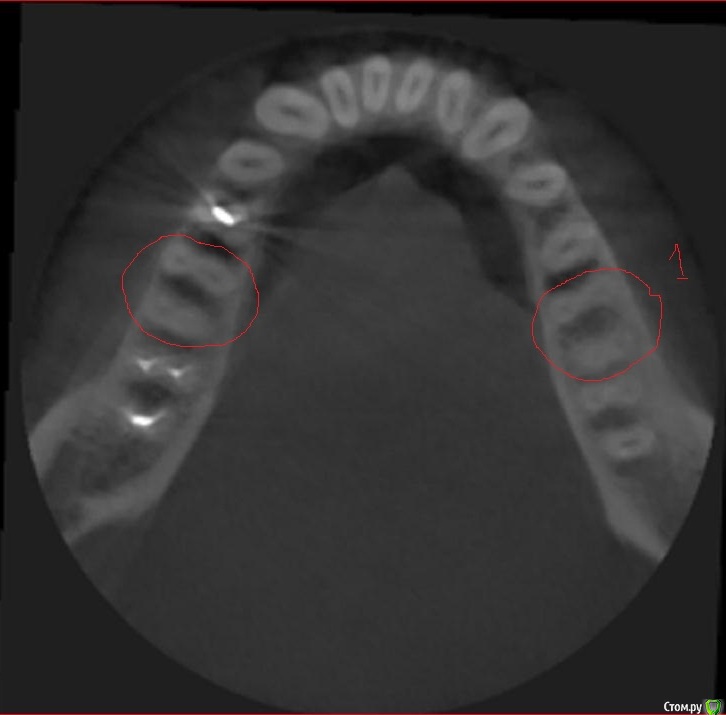

Svetic Опубликовано 16 августа, 2015 Поделиться Опубликовано 16 августа, 2015 (изменено) Здравствуйте, история такая. Отправилась лечить нижнюю шестерку. Выпала пломба, зуб реагировал на холодное и на накусываение. Врач поставила пломбу,депульпировать не стала. Зуб заболел через два дня. Четыре дня назад удалили нерв, реакция зуба на холодное осталась. Позвонила по телефону врачу, говорит что после мышьяка болеть зуб не может. Мог ли врач пропустить один канал? Нашла томограму которую делала 3 месяца назад. Скажите пожалуйста сколько в шестерках каналов? Врач пролечила 3 канала. Тот зуб под номером 1 еще до лечения. Изменено 16 августа, 2015 пользователем Svetic Ссылка на комментарий

St. Опубликовано 16 августа, 2015 Поделиться Опубликовано 16 августа, 2015 Каналов 4. КТ доктор во время лечения видел? Ссылка на комментарий